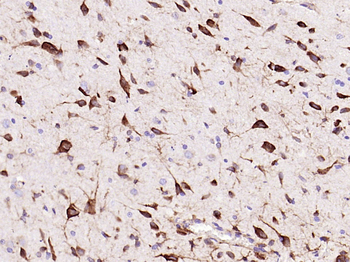

50 μl, 100 μl - MARK3 Recombinant Rabbit Monoclonal Antibody [orb704310]Featured

ICC, IF, IHC-Fr, IHC-P

Human, Mouse

Rat

Rabbit

Recombinant

Unconjugated

50 μl, 100 μl - Featured